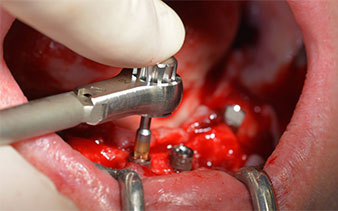

Le trou mentonnier doit d'abord être identifié comme une structure anatomique limitante, puis l'os cortical de la crête a été régularisé avec une pièce à main droite et une fraise sphérique de grande taille (Fig. 4).

C'est ici que l'Implantmed révèle ses premiers avantages. Le protocole chirurgical est prédéfini et les réglages sont enregistrés à des positions fixes. Les positions individuelles peuvent être sélectionnées en appuyant sur la position "P" de la commande au pied ou sur l'écran. La vitesse de 35,000 tr./min. à la position 1 dans ce cas apparaît aussi par de grands chiffres sur l'écran rétroéclairé (Fig 5 et 6).

Le protocole chirurgical préconisé pour les implants utilisés (SKY, Bredent Medical) précise une vitesse de rotation de 1.200 tr./min. pour le pré-forage (Fig. 7 - 9).

Ceci correspond à la position suivante prédéfinie dans l'Implantmed. Nous voyons ici le contre-angle W&H tenu à un angle de 45° par rapport à la crête dans la région de 45 afin de préserver le nerf mentonnier. Le trou mentonnier sert de repére anatomique à tous les forages de cette région. Les forages suivants ont été effectués à la vitesse réduite de 300 tr./min. (Fig. 10 et 11).